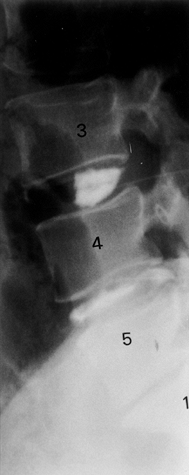

plain radiographic changes. The cardinal findings of LS are endplate

sclerosis and loss of disc space. Radiographs may also show a loss of

lordosis, subluxations, vacuum phenomenon, and osteophytes (Fig. 145.9). Radiography, however, can be misleading: Frymoyer et al. (24) showed that signs suggestive of disc degeneration were present in 90% of adults studied, whereas 53% had no history of LBP (Table 145.5).

![]() |

|

Figure 145.9. Plain radiographic findings of DDD: disc space loss, endplate sclerosis, and osteophyte formation.